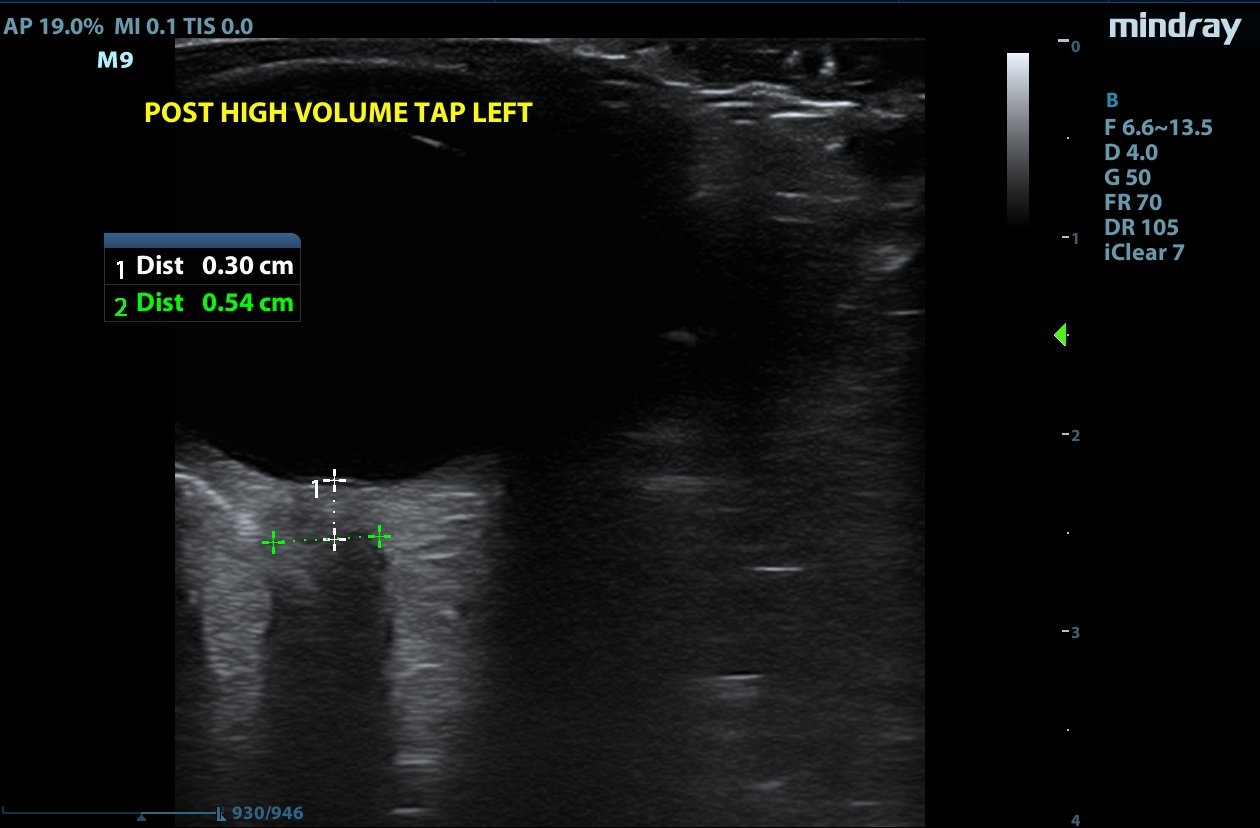

Optic nerve sheath diameter (ONSD) was measured via ultrasound with diameter 5.7mm on left and 6.2mm on right. In order to measure ONSD via optic ultrasound the high-frequency linear array probe (7.5-10-MHz or higher) is utilized in B-mode. The patient is positioned supine and an occlusive dressing, such as Tegaderm, is placed over a closed eyelid with copious conductive gel on top of the dressing. Being careful not to put pressure on the globe, an axial cross-sectional image of the globe is obtained. As demonstrated in the image “annotated left eye ONSD pre-lumbar puncture,” there are two main anechoic areas of the globe, the anterior chamber and the vitreous humor. These anechoic structures are separated by the hyperechoic iris, which surfaces the hyper-echoic-lined lens. At the back of the vitreous humor is the retina, which leads posteriorly into the optic nerve. The optic nerve is the hypoechoic structure posterior to the retina and surrounded by the hyperechoic subarachnoid space, which is encased by the hypoechoic dura mater. The outer edge of the hypoechoic dura matter is where the ONSD is measured.1 The user applies calipers to measure 3mm perpendicularly behind the retina along the hypoechoic optic nerve, and at this level the transverse dimensions of the ONSD are measured using calipers as shown in the images.

Computed tomography (CT) of the head was performed and showed no abnormalities. Lumbar puncture was performed in left lateral decubitus position revealing elevated opening pressure of 29cm H2O. Thirty-five mL of clear cerebral spinal fluid was drained and was negative for all infectious studies.  Optic nerve sheath diameter was again measured post-lumbar puncture with diameters 5.4mm on left and 5.4mm on right.